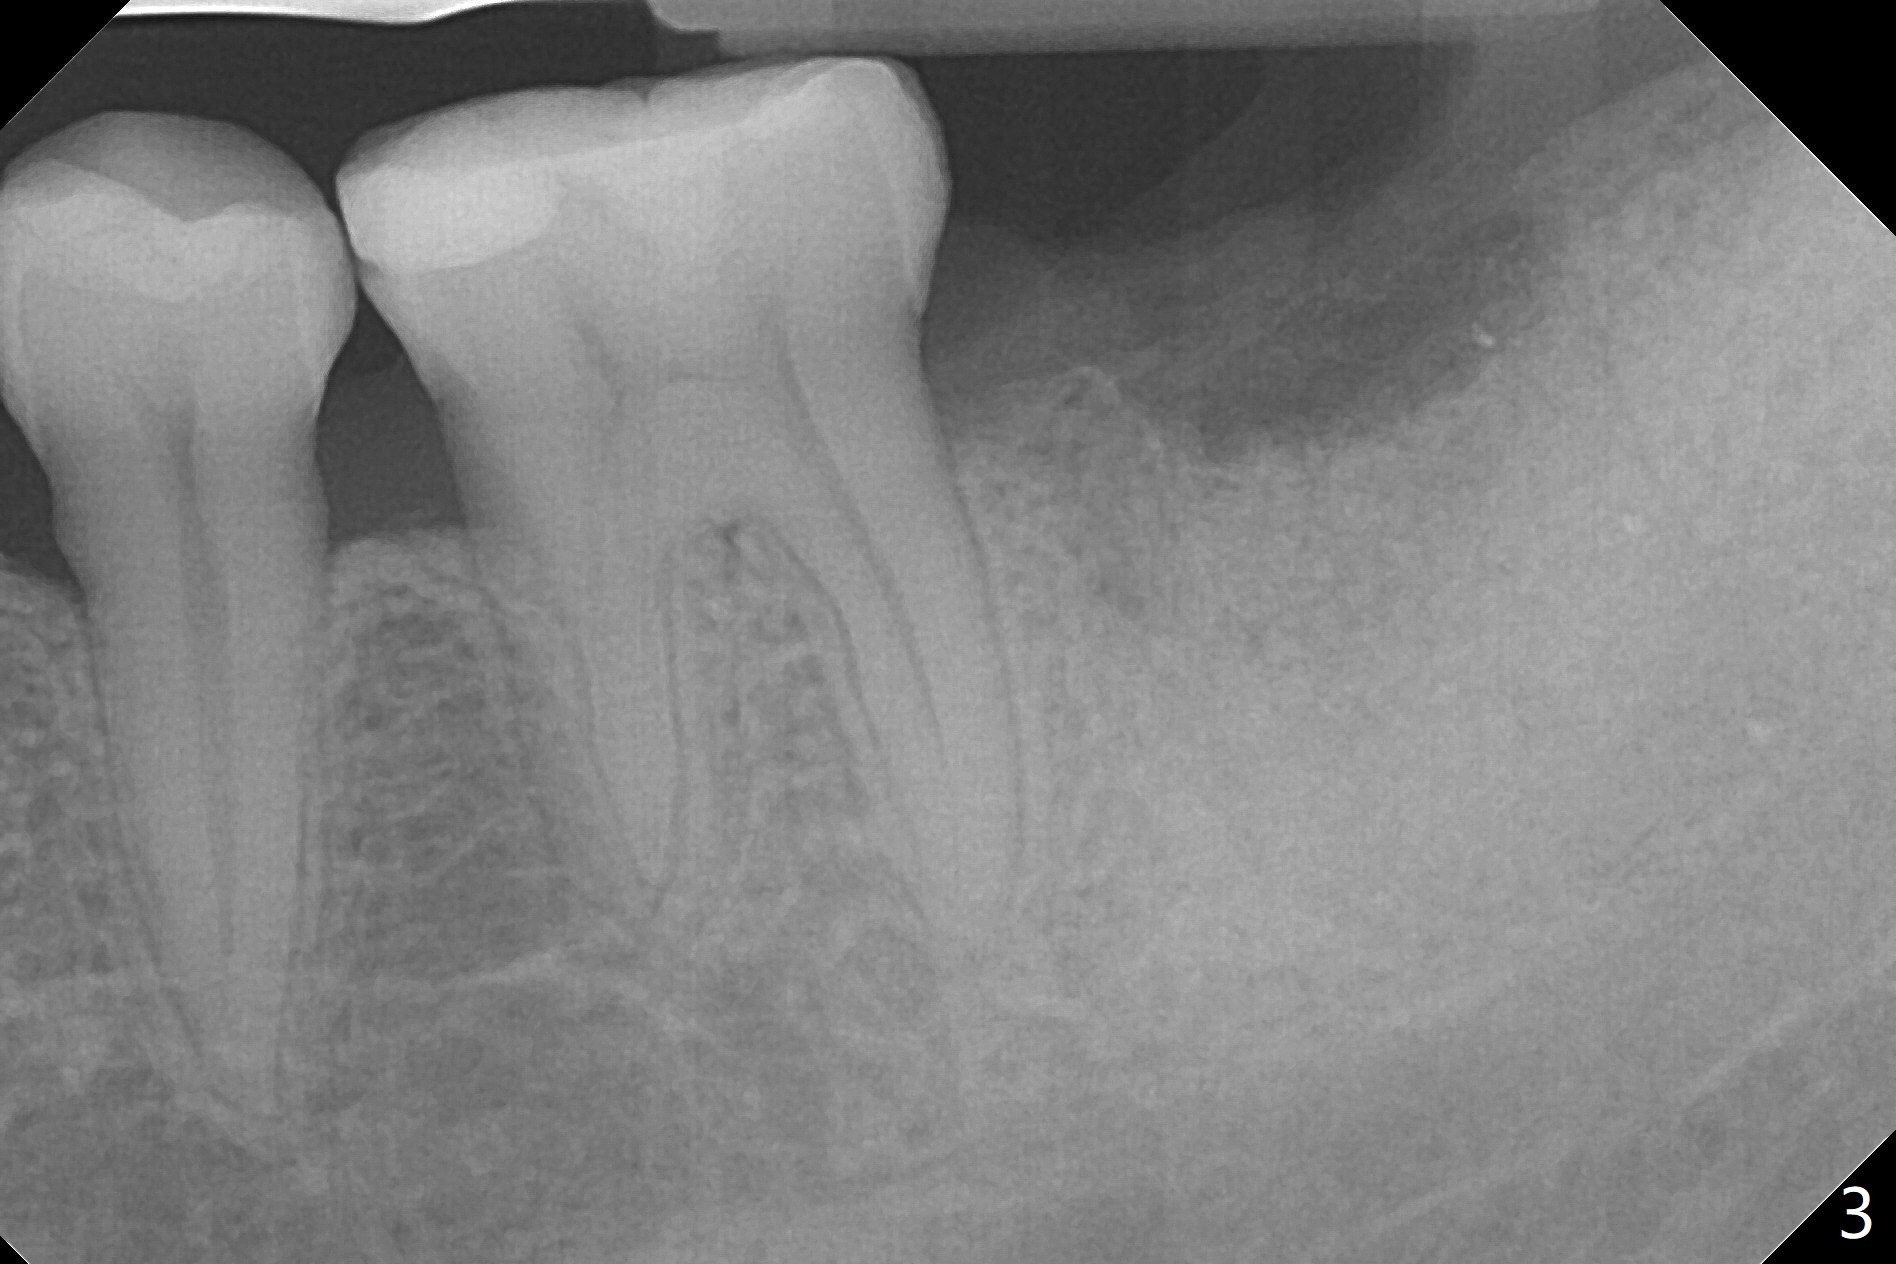

The patient with chronic buccal abscess at #31 is nervous. After extraction, a 7x11 mm tapered implant drops into the single socket, which is close to the Inferior Alveolar Canal (Fig.2). The bottom of the socket is sensitive to manipulation (explorer) after infiltration anesthesia. A 8x14 mm tapered tap is placed without binding, neither is a 8x14 mm cylindrical implant. The implant stability does not increase when Vera (.2-1.0 mm) or Vanilla (.5-1.0 mm) Graft is placed. Socket preservation is finished with Collagen plug and 6-month membrane (Fig.3,4).